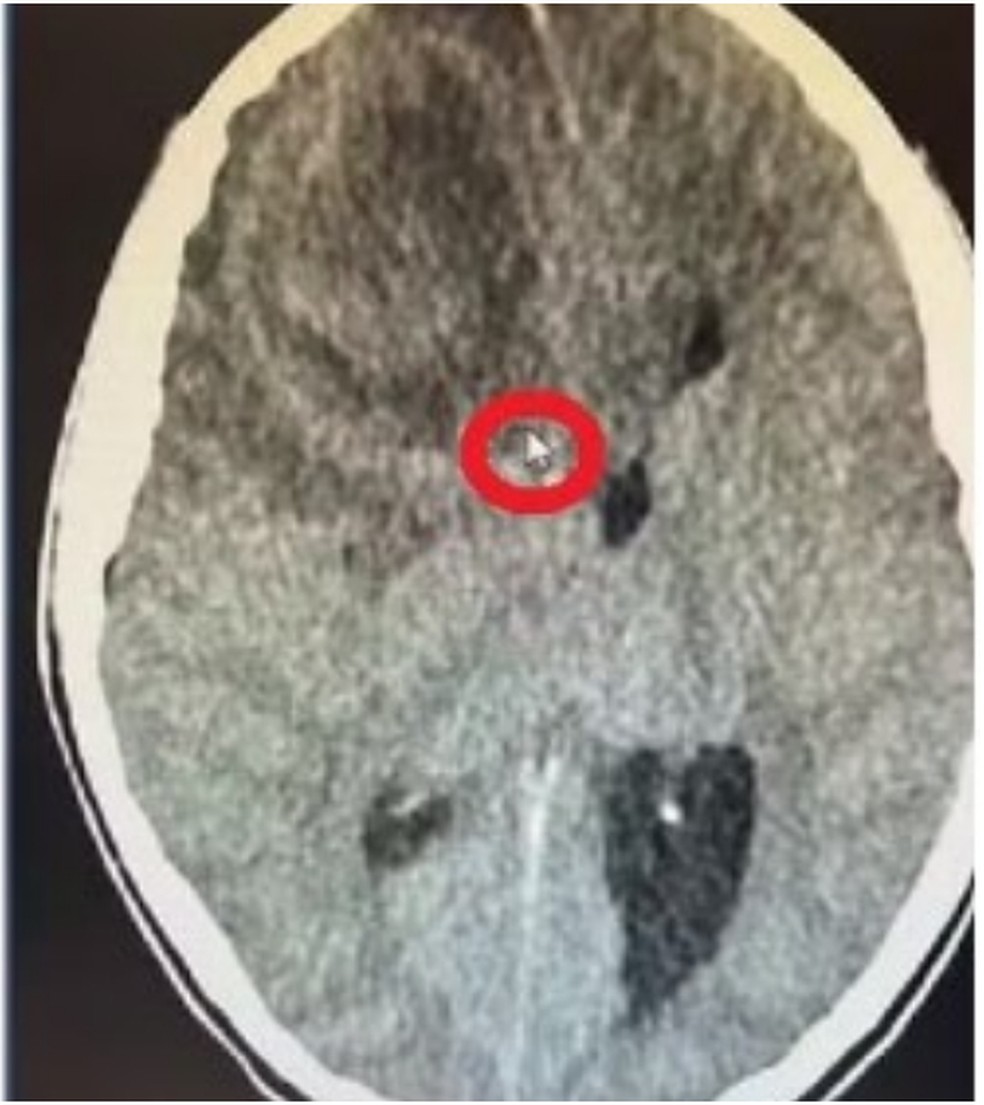

Um novo exame em Millena, esse de tumografia, detectou uma massa de 5 centímetros no cérebro dela. Segundo a família, os médicos disseram que o diagnóstico do que aquilo era não foi preciso.

“Só que não se sabe se essa massa era um tumor, um cisto, um edema, um coágulo… porque não conseguiram abrir a cabeça dela para ver”, falou Thays.

E que, de acordo com o histórico médico dela, a criança estava com “cefaléia há 6 dias” e “coma há 1 dia”. Ainda teve “processo expansivo” relacionado ao “SNC” (Sistema Nervoso Central), de acordo com a “tomografia” realizada em 29 de abril. Que informou haver “diagnóstico diferencial neoplasiva” (formação de um novo tecido anormal, que pode ser benigno ou maligno, como um tumor) “não definido”.